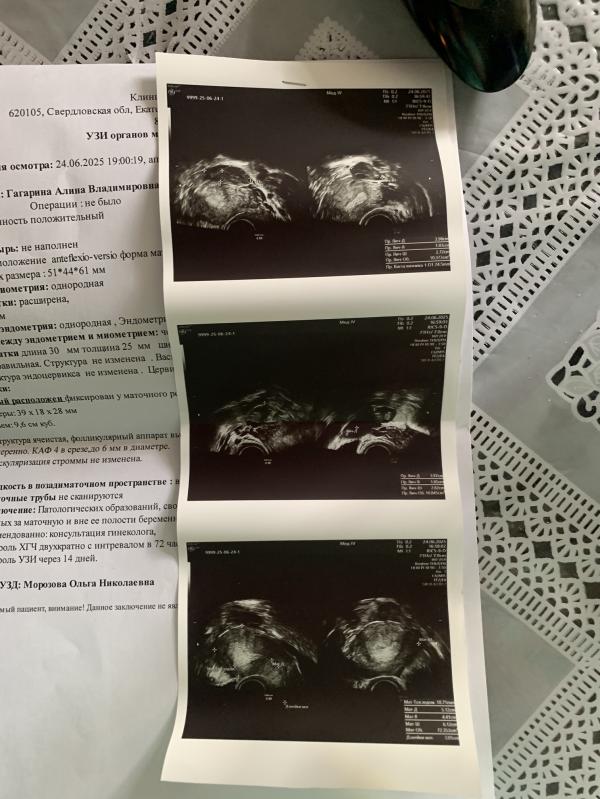

Овуляция была с левой стороны ( слава богу боли у меня в правом 🤣у меня два яичника соединены с маткой рубцами и видимо из за увеличение матки тянет с правой стороны )

Эндометрий хороший и желтое тело вроде прям шикарное ) сказала за хгч она , но я сказала не хочу ждать и нервничать 🤣она говорит ну и хорошо, жду через две недели на узи слушать сердцебиение 😻